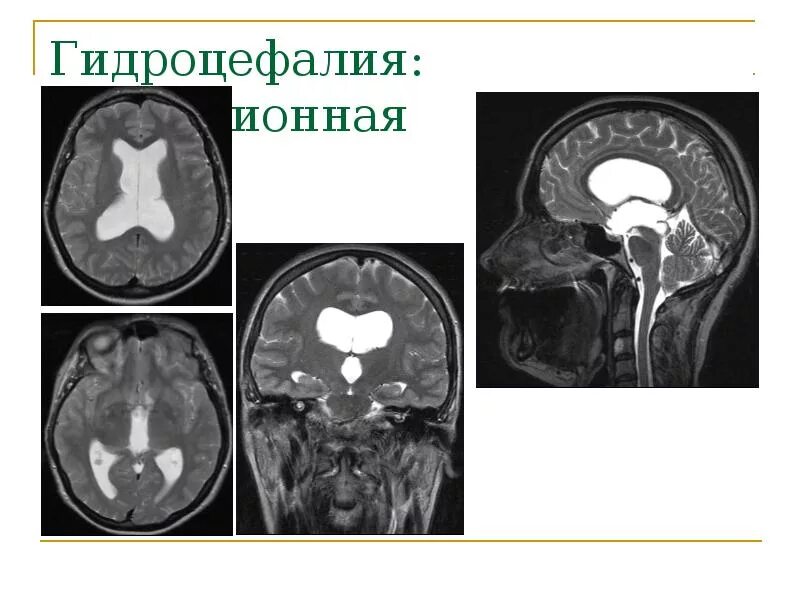

Умеренная гидроцефалия головного мозга у взрослых